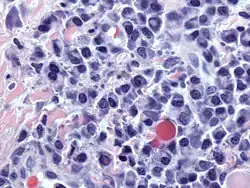

-

Bone marrow aspirate showing the histologic correlate of multiple myeloma under the microscope, H&E stain -

Plasmacytoma, H&E stain -

Micrograph showing myeloma cast nephropathy in a kidney biopsy: Hyaline casts are PAS positive (dark pink/red – right of image). Myelomatous casts are PAS negative (pale pink – left of image), PAS stain. -

Atypical plasma cell infiltrate with both Russell (cytoplasmic) and Dutcher (nuclear) bodies (H&E, 50x) -

Histopathology

A bone marrow biopsy is usually performed to estimate the percentage of bone marrow occupied by plasma cells. This percentage is used in the diagnostic criteria for myeloma. Immunohistochemistry (staining particular cell types using antibodies against surface proteins) can detect plasma cells that express immunoglobulin in the cytoplasm and occasionally on the cell surface; myeloma cells are often CD56, CD38, CD138, and CD319 positive and CD19, CD20, and CD45 negative.[21] Flow cytometry is often used to establish the clonal nature of the plasma cells, which will generally express only kappa or lambda light chain. Cytogenetics may also be performed in myeloma for prognostic purposes, including a myeloma-specific fluorescent in situ hybridization and virtual karyotype.

The plasma cells seen in multiple myeloma have several possible morphologies. First, they could appear like a normal plasma cell, a large cell two or three times the size of a peripheral lymphocyte. Because they are actively producing antibodies, the Golgi apparatus typically produces a light-colored area adjacent to the nucleus, called a perinuclear halo. The single nucleus (with a single nucleolus with vesicular nuclear chromatin) is eccentric, displaced by an abundant cytoplasm. Other common morphologies seen, but which are not usual in normal plasma cells, include: